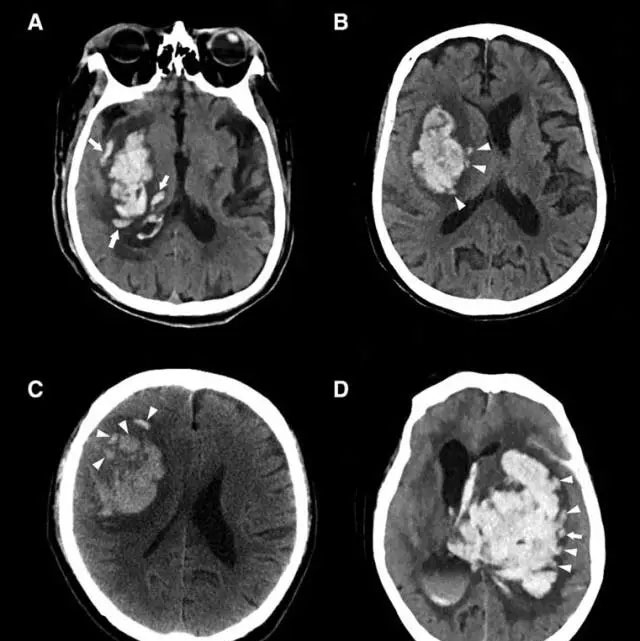

李琦提出的“岛征”反映了一种特殊类型血肿,其特征主要反映出血肿周围的多灶性小出血,在阅读CT片时,李琦发现形似海岛的血肿更容易扩大,因此以“岛征”命名了该征象,“岛征”满足以下两个标准中的任一条件即可定义:(1)存在≥3个分散小血肿全部与主要血肿分离(上图A至C)或(2)存在≥4个小血肿,部分或全部与主要血肿相连(上图D)。分散的小血肿(恰似分离的小岛)可以是圆形或椭圆形,与主要血肿分开。

研究中,李琦对起病6小时内进行颅脑CT扫描的自发性脑出血患者进行了反复研究,发现其中41例(16.3%)在基线CT上发现岛征,另外,在85名血肿扩大的患者中有38名(44.7%)患者观察到岛征,岛征预测血肿扩大具有很高的特异性,也就是说,岛征阳性几乎意味着脑出血患者血肿扩大,同时也预示脑出血患者的不良预后。